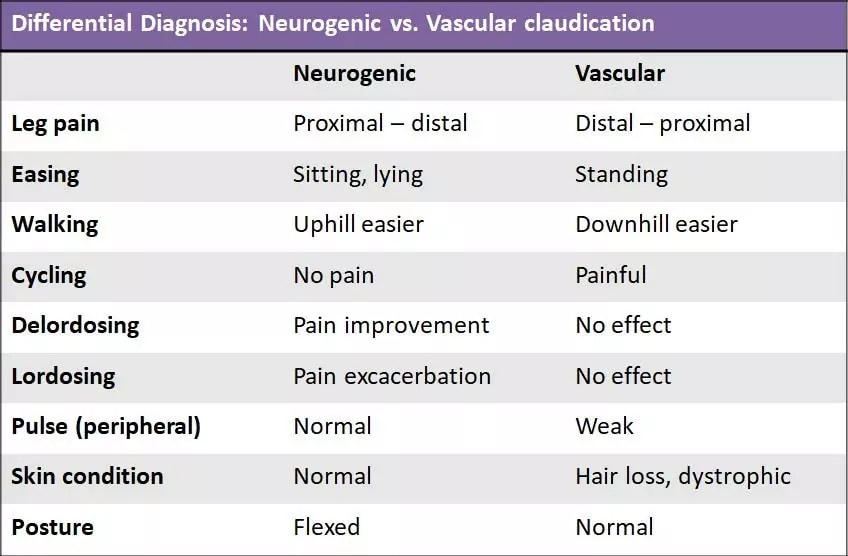

Det är viktigt att skilja mellan neurogen claudicatio intermittens och vaskulär claudicatio. I följande tabell visas skillnaderna mellan de två villkoren:

Nadeau et al. (2013) har jämfört individuella tecken och symtom avseende deras förmåga att skilja mellan de två tillstånden. De fann att smärtlindrande faktorer och symtomens lokalisering hade svag klinisk betydelse för neurogen claudicatio och vaskulär claudicatio. De mest utmärkande dragen för ett neurogent ursprung var:

- En positiv skylt för kundvagn

- Symtom lokaliserade ovanför knäna

- Provokation i stående ställning och lindring i sittande ställning var mycket sannolika.

Genom att kombinera dessa egenskaper erhölls en positiv sannolikhetskvot på 13. Patienter med symtom i vaden som lindrades när de stod upp hade en stark sannolikhet för vaskulär claudicatio (LR+ 20).